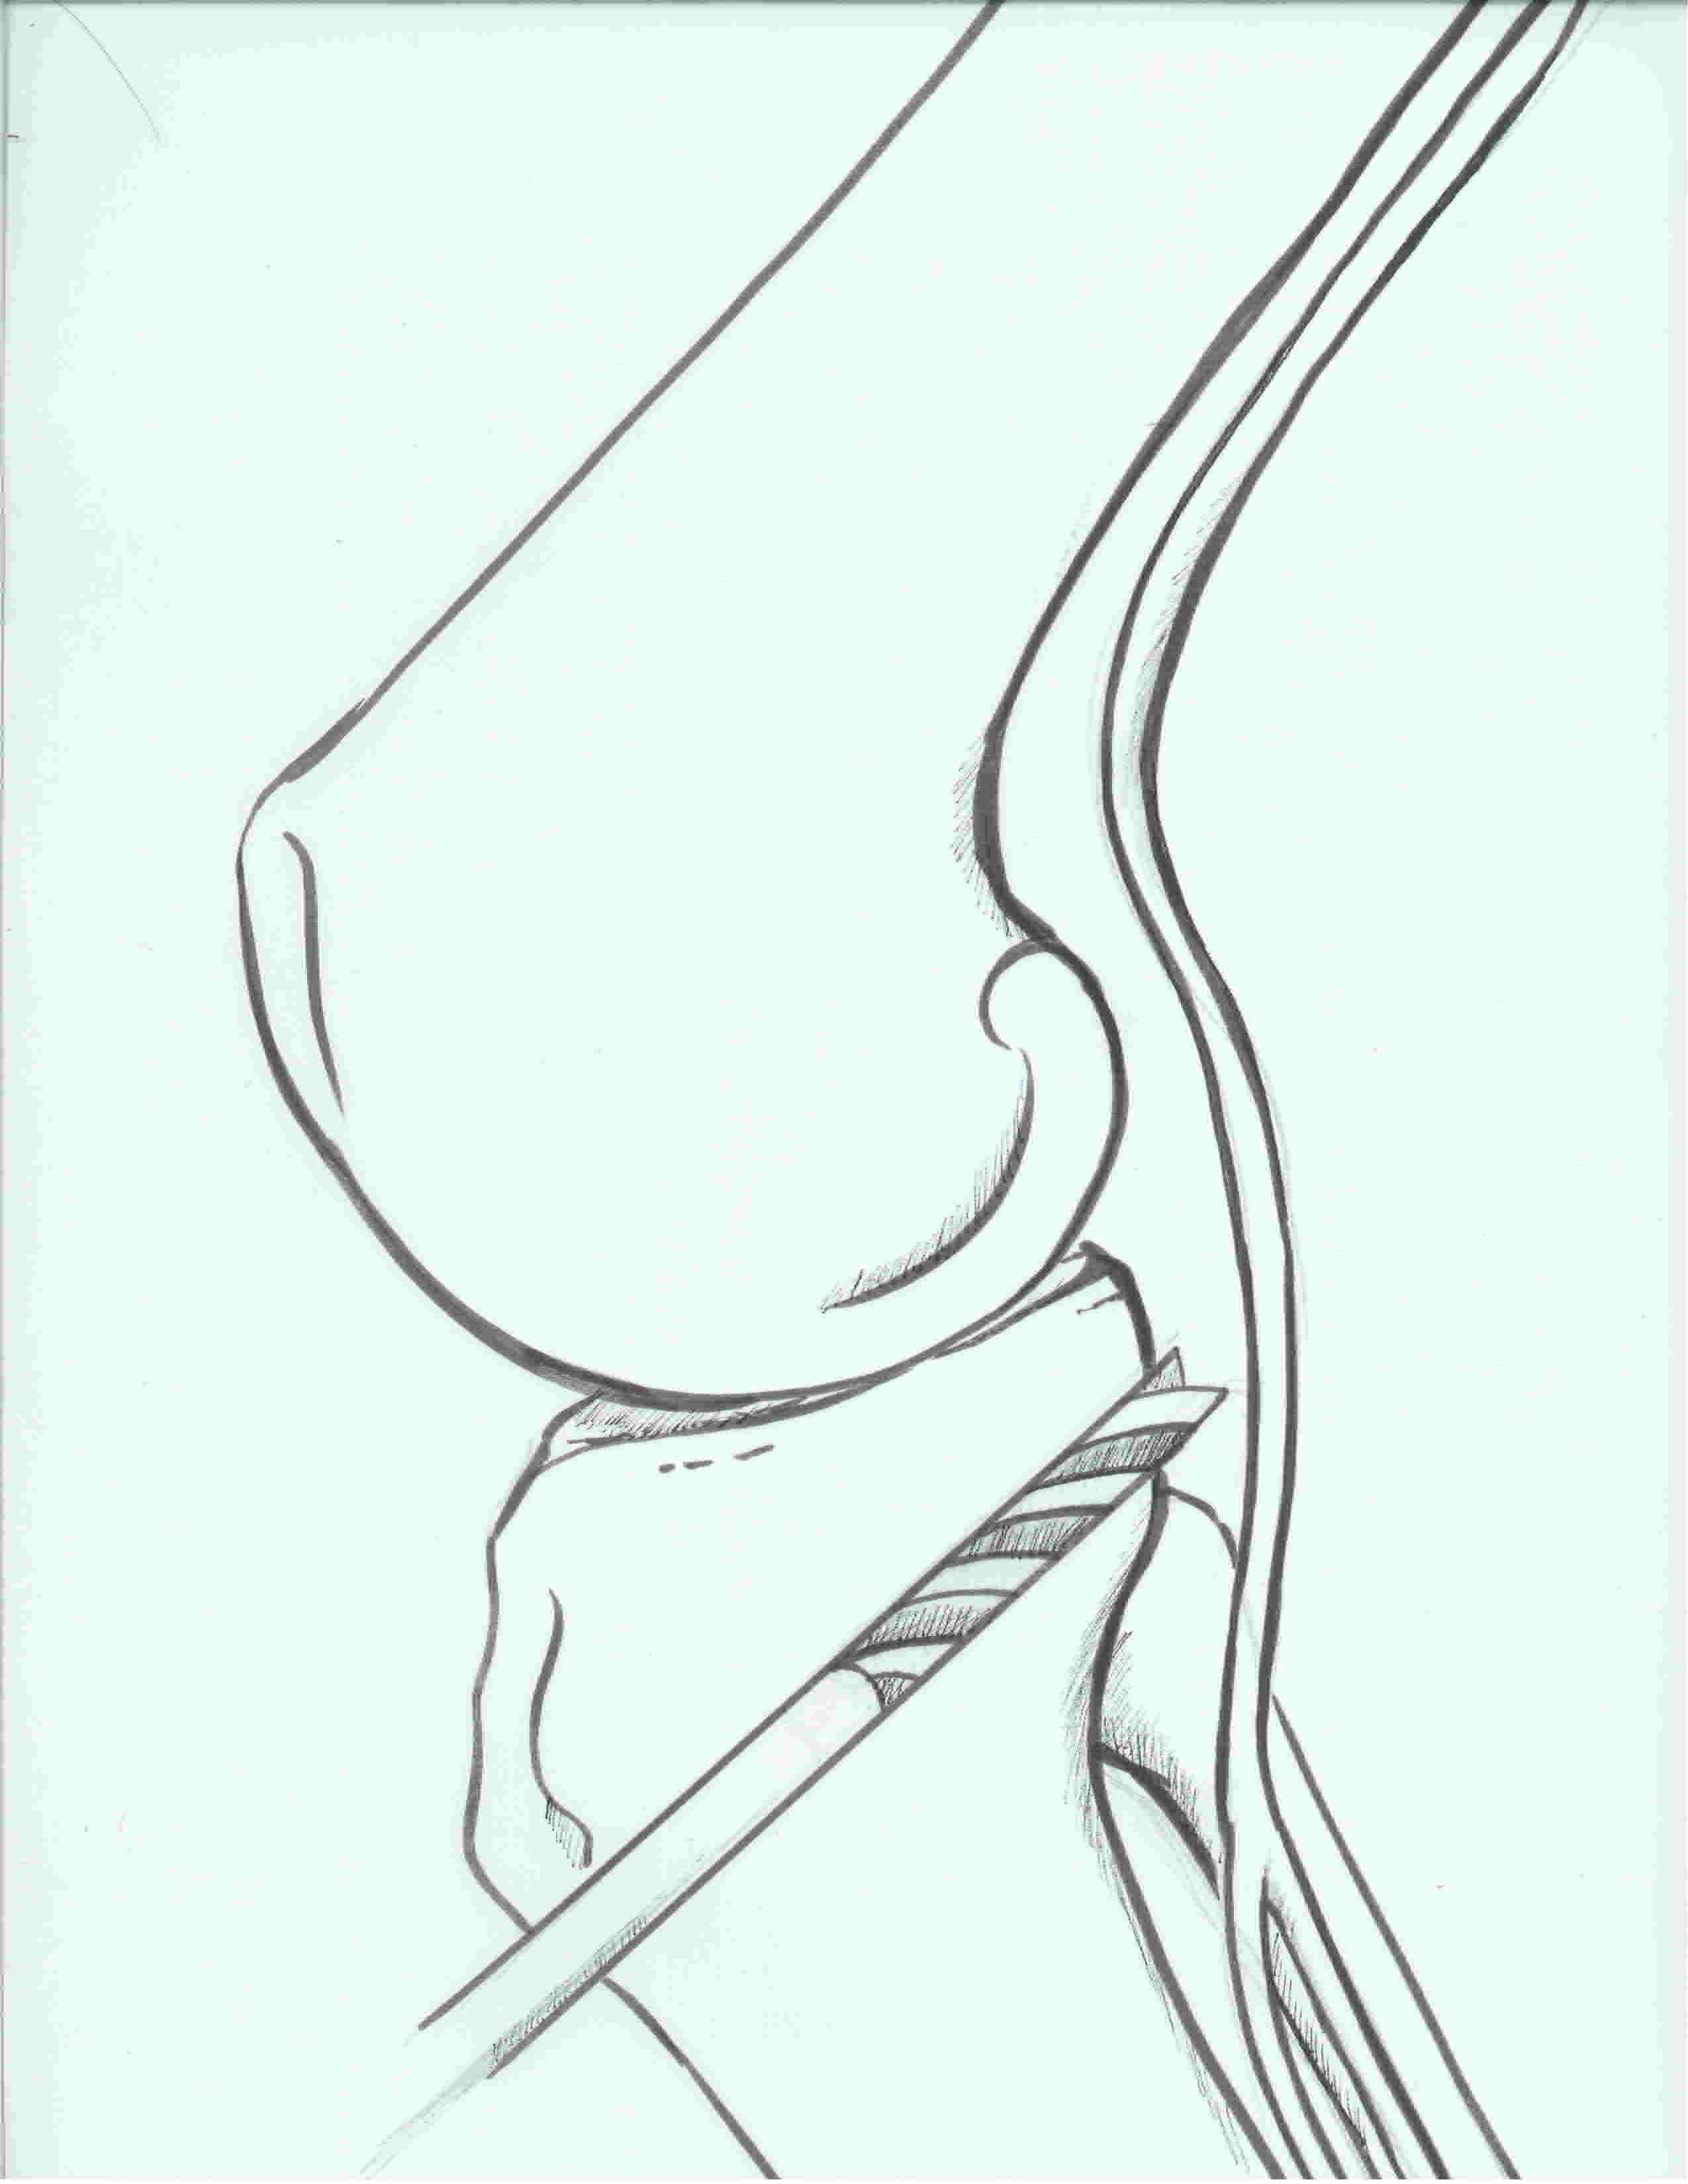

Tibial Tunnel

Incision medial to tibial tuberosity

- PCL jig inserted, usually set at 60 or 65o

- under fluoroscopy, identify the PCL facet

- at least 1 cm below the articular surface

- needs to be more lateral than medial to recreate the anterolateral bundle of PCL

- curette inserted to protect NV bundle

- knee in flexion to protect NV bundle

- beath pin passed

- ream appropriate tunnel (9 or 10 mm for achilles tendon allograft)

PCL tibial tunnelPCL DrillTibial Tunnel PCL